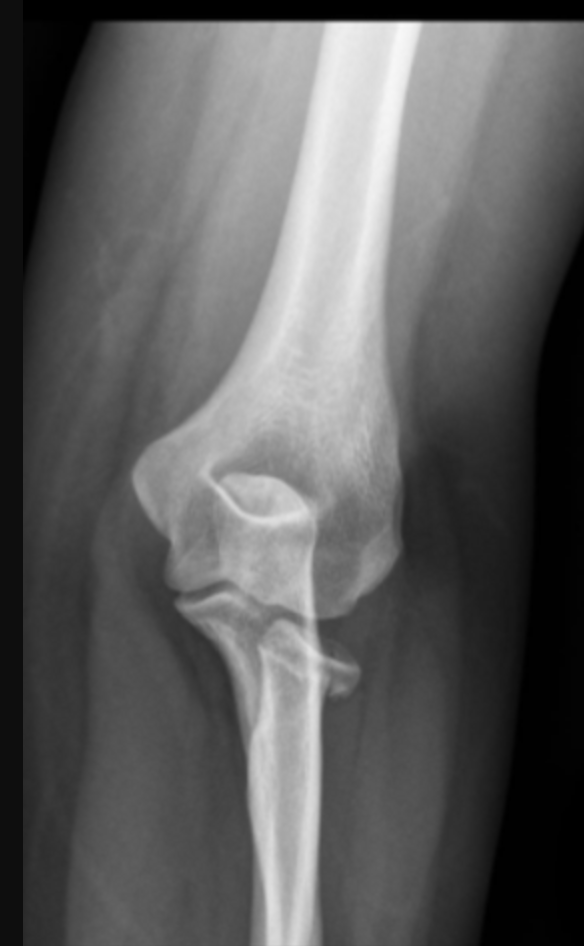

Mecanismo de lesion de esta fractura

Fractura de la parte LATERAL del radio —> rotacion externa con carga axial al codo con fuerza combinada de valgo

Fractura de la parte INTERNA del radio —> rotacion interna con carga axial al codo con fuerza combinada de valgo

Clasificacion de Mason de esta fractura

Tipo 1: fisura o fractura marginal con <2mm de desplazamiento

Tratamiento de fractura de mason tipo 1

Cabestrillo

Tipo 2: Fractura marginal desplazada >2mm (en este caso hacia abajo)

Tratamiento de fractura de mason tipo 2

Reseccion de fragmento si es muy pequeño para fijar

Fijacion interna con tornillo o minimplante

Clasificacion de fractura de mason de esta fractura

Tipo 3 —> conminutada

Tratamiento de la fractura de mason tipo 3

Protesis de silicon o metalica

Clasificacion de mason de estas fracturas

Tipo 4 —> fractura de cabeza radial asociada a luxacion de codo

Tratamiento de fractura tipo 4 de mason

Protesis de silicon o metal